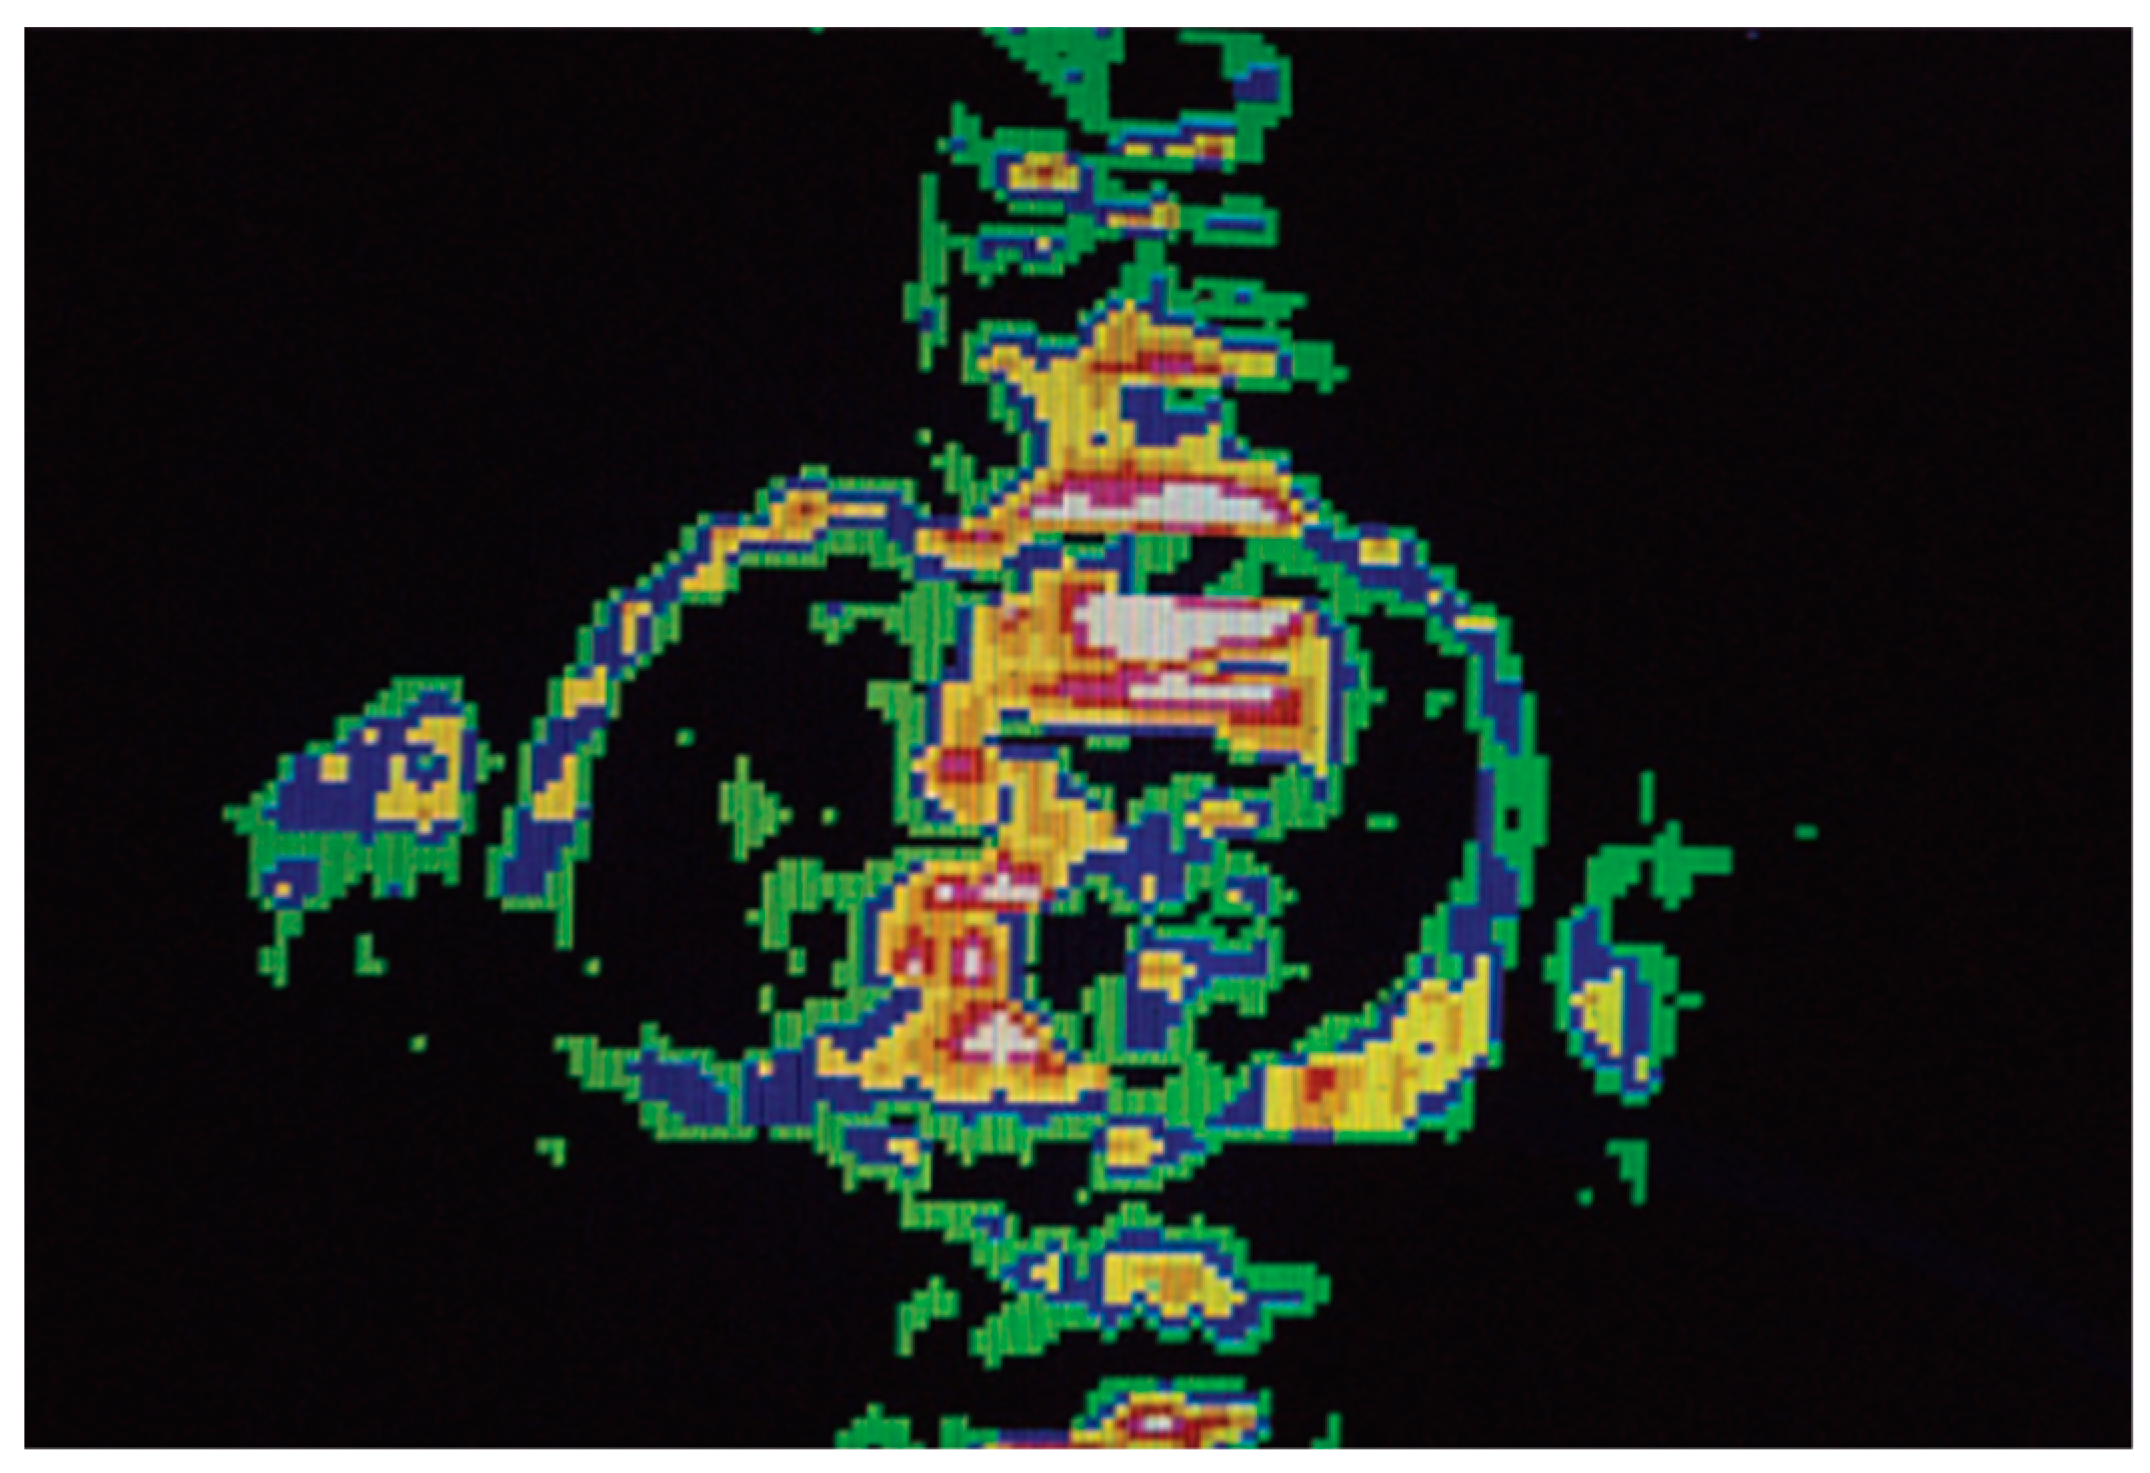

- Ma, L.E.; Yerly, J.; Piccini, D.; Di Sopra, L.; Roy, C.W.; Carr, J.C.; Rigsby, C.K.; Kim, D.; Stuber, M.; Markl, M. 5D Flow MRI: A Fully Self-gated, Free-running Framework for Cardiac and Respiratory Motion-resolved 3D Hemodynamics. Radiol. Cardiothorac. Imaging. 2020, 2, e200219. [Google Scholar] [CrossRef] [PubMed]